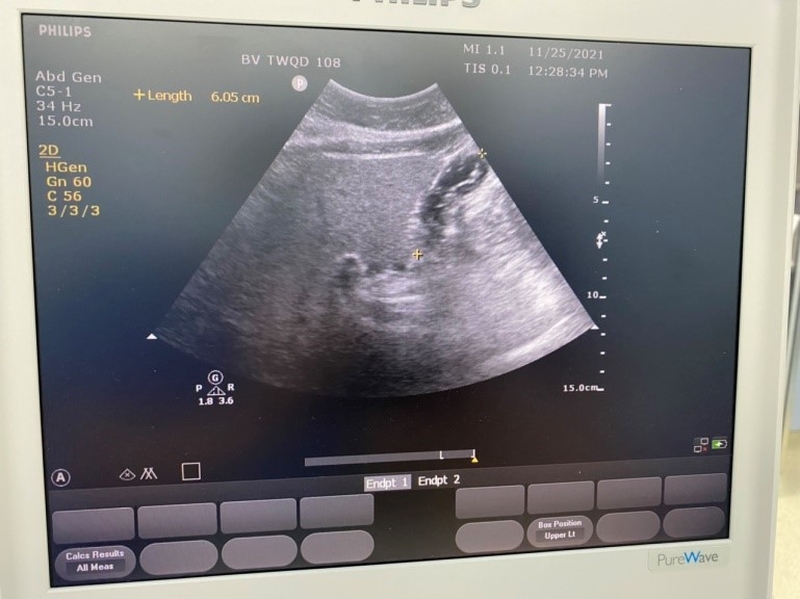

Siêu âm dạ dày là phương pháp sử dụng sóng siêu âm (cao tần) để phát hiện những bất thường trong dạ dày và có thể tầm soát ung thư dạ dày. Phương pháp siêu âm dạ dày tổng quát giúp người bệnh nhận biết những bất thường về dạ dày, đường tiêu hóa nếu có để đưa ra phương pháp điều trị phù hợp nhất, đạt hiệu quả tốt nhất.

Siêu âm dạ dày là phương pháp sử dụng sóng siêu âm (cao tần) để phát hiện những bất thường trong dạ dày Siêu âm dạ dày giúp phát hiện những bất thường trong dạ dày